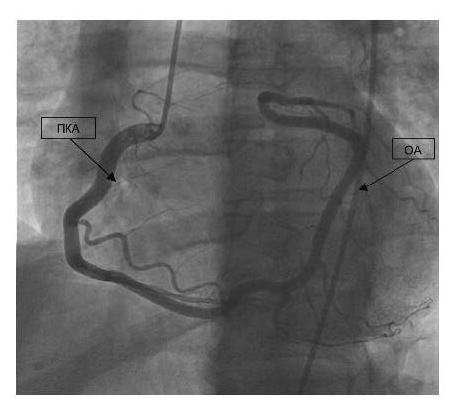

По экстренным показаниям выполнена коронароангиография. Заключение: аномалия развития КА. Единственная КА отходит от правого коронарного синуса. Правая КА (ПКА) формирует переднюю межжелудочковую артерию (ПМЖА), огибающую артерию (ОА). ПМЖА с ровными контурами заполнения, на границе среднего и дистального сегментов окклюзирована. Постокклюзионное русло удовлетворительно заполняется по внутрисистемным коллатералям. ОА и ее ветви с ровными контурами наполнения, без стенозов. ПКА отдает конусную ветвь, ветвь к правому желудочку, ветвь острого края, заднее – боковые ветви (ЗБВ 1 и ЗБВ 2 ПКА) и заднюю межжелудочковую ветвь ПКА, ПКА и ее ветви с ровными контурами наполнения, без стенозов. Заключение: аномальное развитие КА – единственная КА. Окклюзия ПМЖА на границе среднего и дистального сегментов.

Результаты коронарографии представлены на рис. 2.

Рис. 2. Коронарография больного М. от 13.10.2018.